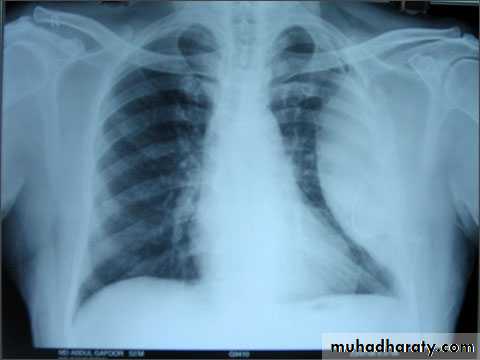

hydropneumothorax

If both a pneumothorax and a pleural effusion occur together, it is called a hydropneumothoraxA hydropneumothorax is usually due to trauma, surgery, bronchopleural fistula

It is characterized by an air-fluid level in the hemithorax

A straight edge,indicative of a fluid interface, in this case an air-fluid interface, is seen on the right.